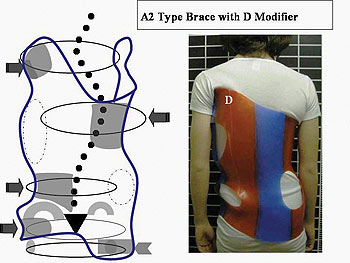

الضغط الصحيح لحزام اعوجاج العمود الفقري: الضلع أم الفقرة؟ عندما يُشخَّص الطفل أو المراهق بوجود اعوجاج في العمود الفقري، يبدأ الأهل في البحث عن أفضل طرق العلاج غير الجراحي. ويعد حزام اعوجاج العمود الفقري

ضغط حزام اعوجاج العمود الفقري : كيف يؤثر على العضلات والعظام والأقراص بين الفقرات؟ يعاني بعض الأطفال والمراهقين من اعوجاج العمود الفقري مجهول السبب عند المراهقين، وهي حالة يحدث فيها انحناء غير طبيعي في